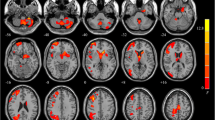

Metabolic analysis

Compared with the PET controls, ECTS patients showed distributed hypo-metabolism in the bilateral caudate, putamen, pallidum, lateral orbitofrontal gyri, rostral middle frontal gyri, superior frontal gyri, left thalamus, NAc, right caudal middle frontal gyrus, and right frontal pole (Supplementary Fig. S1). Regional analysis was performed on these ROIs (Table 3), and significantly decreased regional metabolism was found in bilateral caudate, putamen, pallidum, left NAc, right rostral middle frontal gyrus, and frontal pole of ECTS patients (P < 0.05, FDR corrected) (Fig. 3). Pearson’s correlation analysis showed that only the SUVR of the right caudate was positively related with PSI (P = 0.034) (Fig. 4A). The seizure duration, time of AED treatment, and AED treatment types showed no significant influence on regional SUVR (Supplementary Material S2, S3).

Disrupted network connectivity of ECTS

The adjacency matrix of ECTS patients and MRI controls were shown in Supplementary Fig. S2. NBS analysis showed that absolute values of 20 FCs were significantly decreased in ECTS patients compared with MRI controls, which connected 16 distinct ROIs (NBS cluster size threshold = 12) (Table 4). This main subnetwork involved a pathway from rolandic areas to the caudate, thalamus, and the cortical regions, which is part of the cortical–striatal circuit (Fig. 5A). If suprathreshold cluster size test for NBS multiple test correction was avoided, two additional small PSI-related subnetworks could also be found (Fig. 5B–C). The two small subnetworks connected 15 ROIs through 16 FCs (Supplementary Table S1). If PSI-unrelated FCs were also included, connections could be found among the main subnetwork and additional subnetworks (Supplementary Fig. S3). Moreover, ROIs within the main subnetwork was more densely connected than the additional subnetworks.

Network-based statistic analysis results between controls and ECTS patients. Cau, caudate; Ento, entorhinal; FP, frontal pole; Fusi, fusiform; IC, isthmus cingulate; insula, insula; LO, lateral occipital; LOF, lateral orbitofrontal; MT, middle temporal; NAc, nucleus accumbens; Pal, pallidum; Pars, pars triangularis; PC, precuneus; Peri, pericalcarine; PostC, postcentral; PreC, precentral; Put, putamen; RAC, rostral anterior cingulate; SF, superior frontal; SP, superior parietal; ST, superior temporal; Tha, thalamus

Absolute values of FCs within the main NBS subnetwork (P = 0.005) and the additional subnetwork-2 (P = 0.040) were positively correlated with PSI in ECTS patients (Fig. 4B–C). However, the correlation between that within additional subnetwork-1 and PSI was not significant in ECTS patients (P = 0.090). In particular, absolute values of FCs between bilateral rolandic areas (precentral and postcentral gyri) were positively correlated with PSI in ECTS patients (P < 0.001) (Fig. 4D). The seizure duration, time of AED treatment, and AED treatment types showed no significant influence on PSI-related FCs (Supplementary Tables S2 and S3).